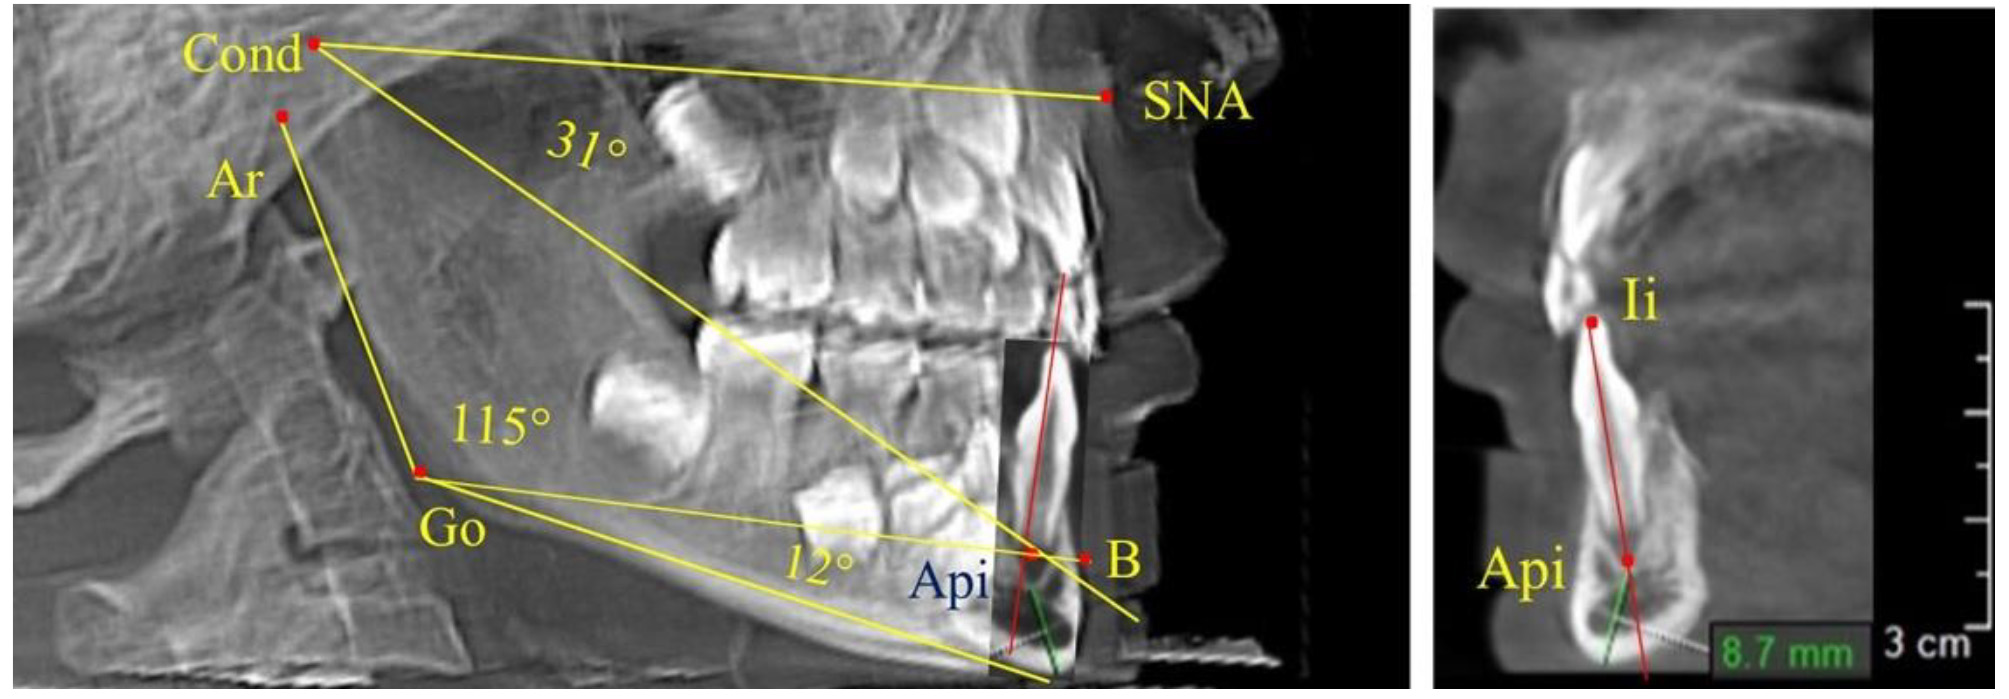

Существенным дополнением к анализу телерентгенограммы предложены методы ее совмещения с фрагментами томограмм [17].

Данная методика позволяла устранить некоторые неточности ТРГ, связанные с наложением на объект исследования рядом расположенных рентгеноконтрастных структур. Данная методика может быть использована при определении положения апикальной точки медиального нижнего резца в ходе исследования гнатического отдела лица.

Особенность анализа телерентгенограммы в периоде сменного прикуса заключалась в том, что наслоение зачатков постоянных зубов затрудняло определение апикальной точки нижнего резца. В подобных случаях использовали метод совмещенного анализа телерентгенограммы с фрагментом томограммы, на котором, также как и на телерентгенограмме, определяли положение резцовой и апикальной точек с построением условной вертикали, которая служила ориентиром для совмещения фрагментов (рис. 2).

Рис. 2. Особенности совмещения телерентгенограммы с фрагментом томограммы в сменном прикусе